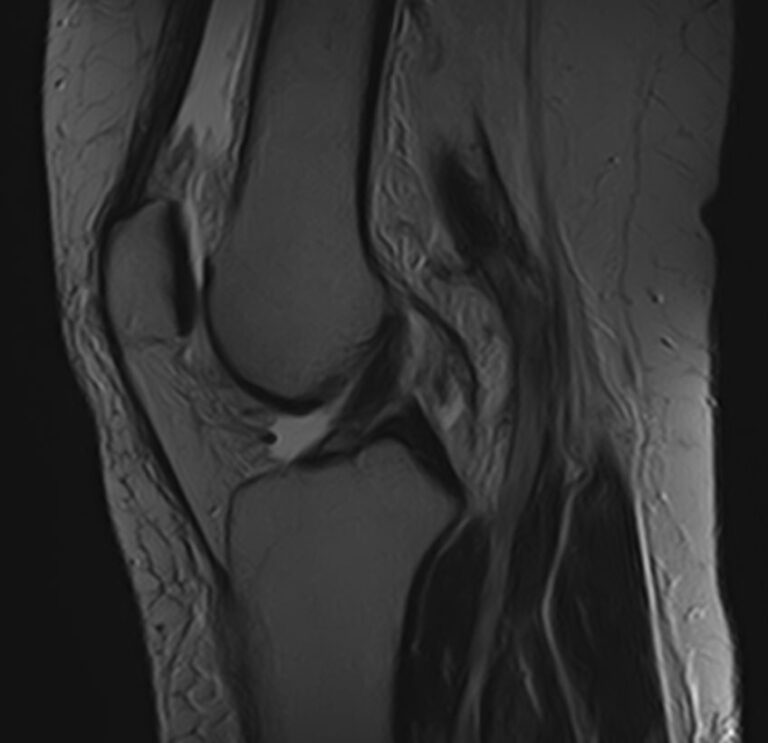

При сочетанном поражении этих анатомических областей целесообразно проведение комплексной МРТ, включающей обследование пояснично-крестцового отдела позвоночника и коленных суставов.

Магнитно-резонансная томография является высокоинформативным методом выявления причин возникновения заболеваний позвоночного столба и суставов. В клинике «Доступная медицина» диагностика осуществляется на новейшем высокопольном томографе закрытого типа TOSHIBA VANTAGE TITAN 1,5 Тесла, обеспечивающем высочайшее качество изображений исследуемой зоны.

Томограф позволяет детально визуализировать состояние всех анатомических структур позвоночного столба на исследуемом уровне, костные структуры колена и окружающие мягкие ткани данных анатомических областей, включая мышцы, связки, нервные сплетение, сосуды.